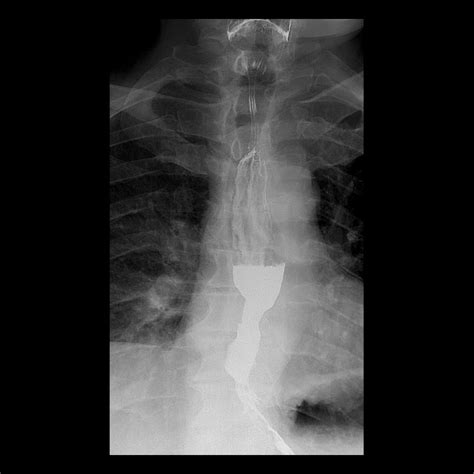

Barium Swallow (Esophagram) An X-ray procedure where the patient swallows a contrast agent (barium) to visualize the shape and contour of the esophagus, highlighting areas of narrowing.